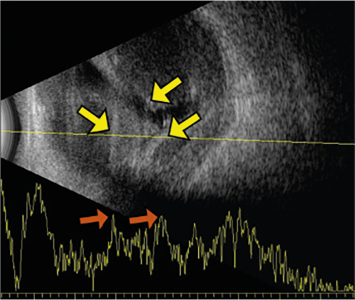

Figura 29-3. DCH. Ultrasonido modo B y modo A

Figura 29-3. DCH. Ultrasonido modo B revela engrosamiento coroideo múltiple con elevación de alta reflectividad (flechas amarillas). El modo A muestra picos elevados en las áreas del DCH (flecha naranja).